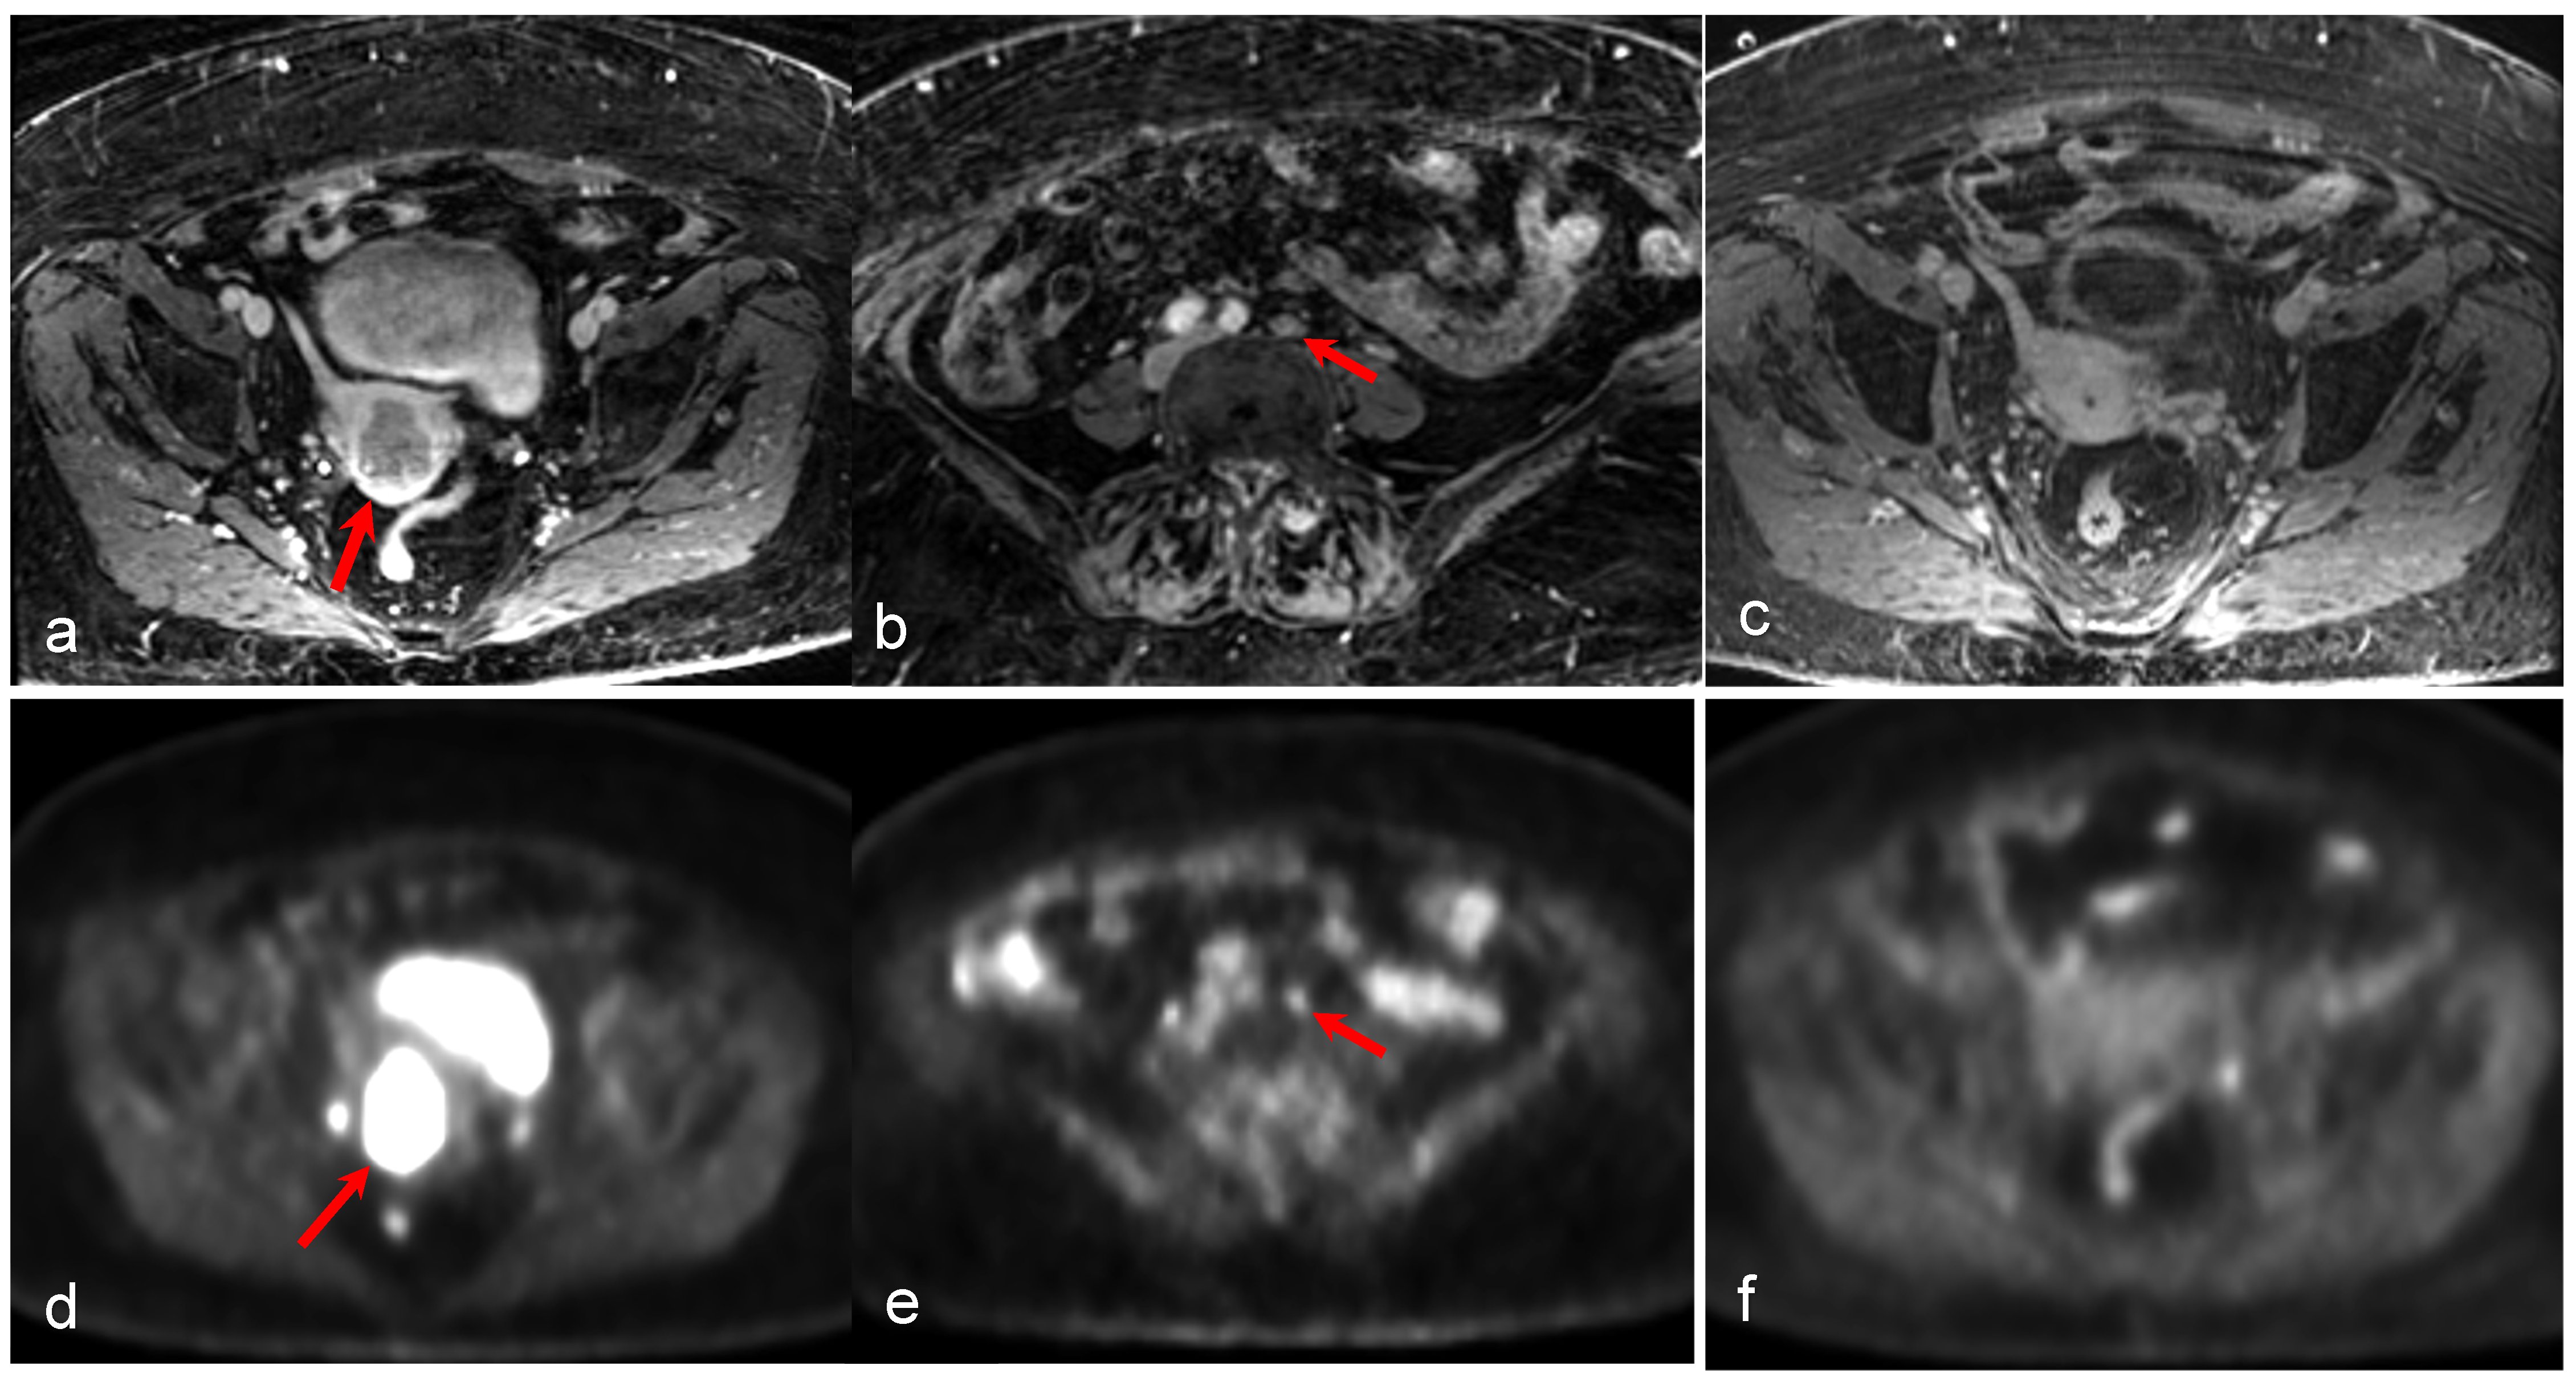

- Tsuyoshi, H.; Tsujikawa, T.; Yamada, S.; Chino, Y.; Shinagawa, A.; Kurokawa, T.; Okazawa, H.; Yoshida, Y. FDG-PET/MRI with high-resolution DWI characterises the distinct phenotypes of endometrial cancer. Clin. Radiol. 2020, 75, 209–215. [Google Scholar] [CrossRef] [PubMed]

- Tsuyoshi, H.; Tsujikawa, T.; Yamada, S.; Okazawa, H.; Yoshida, Y. Diagnostic value of 18F-FDG PET/MRI for staging in patients with endometrial cancer. Cancer Imaging 2020, 20, 75. [Google Scholar] [CrossRef]

- Kitajima, K.; Suenaga, Y.; Ueno, Y.; Kanda, T.; Maeda, T.; Takahashi, S.; Ebina, Y.; Miyahara, Y.; Yamada, H.; Sugimura, K. Value of fusion of PET and MRI for staging of endometrial cancer: Comparison with ¹⁸F-FDG contrast-enhanced PET/CT and dynamic contrast-enhanced pelvic MRI. Eur. J. Radiol. 2013, 82, 1672–1676. [Google Scholar] [CrossRef]

- Ironi, G.; Mapelli, P.; Bergamini, A.; Fallanca, F.; Candotti, G.; Gnasso, C.; Taccagni, G.L.; Sant’Angelo, M.; Scifo, P.; Bezzi, C.; et al. Hybrid PET/MRI in Staging Endometrial Cancer: Diagnostic and Predictive Value in a Prospective Cohort. Clin. Nucl. Med. 2022, 47, e221–e229. [Google Scholar] [CrossRef]